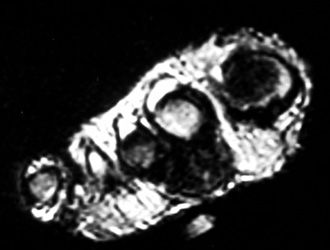

MR appearance: Typically present as persistent intermediate to low signal intensity on T1W and T2W with surrounding inflammation and post contrast enhancement. Bony erosions are also seen well.

44years old male with rapidly enlarging mass in the foot. Radiographs demonstrates soft tissue mass between the 2nd and 3rd toes,with no calcification.Well defined erosion is noted at the radial aspect of the base of proximal phalanx of 2nd toe. Mild soft tissue swelling with faint calcification is also seen at 1st MTP joint ,with small erosion medial aspect of 1st Mt head. MR demonstrates mass is isointense to hypointense on T1W, and T2W images, with minimum bone marrow edema at the base of proximal phalanx of 2nd toe. Erosion is well seen at the base of proximal phalanx of 2nd toe on T1W images.